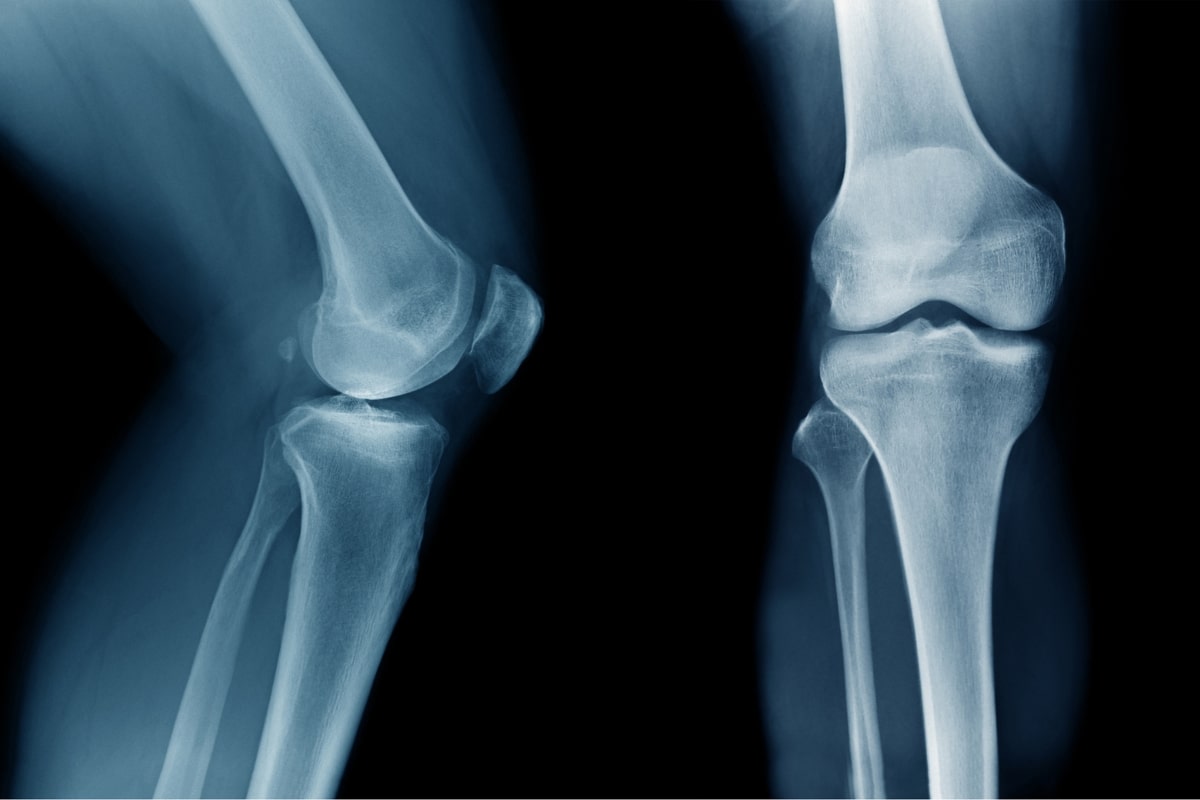

Ανατομία Γόνατος

Το γόνατο είναι μια από τις πιο περίπλοκες και σημαντικές αρθρώσεις του ανθρώπινου σώματος. Αποτελείται από οστά, χόνδρους, συνδέσμους και τένοντες που συνεργάζονται για να επιτρέψουν την κίνηση και να υποστηρίξουν το βάρος του σώματος.

Το γόνατο συνδέει το μηριαίο οστό (μηρό) με την κνήμη (κνήμη) και περιλαμβάνει επίσης την επιγονατίδα (γόνατο). Αυτά τα τρία οστά σχηματίζουν την άρθρωση του γόνατος.

Η κατανόηση της ανατομίας του γόνατος είναι ζωτικής σημασίας για τη διάγνωση και την αντιμετώπιση των προβλημάτων που μπορεί να προκύψουν.

Οι τραυματισμοί ή οι εκφυλιστικές ασθένειες σε οποιοδήποτε από αυτά τα μέρη μπορούν να προκαλέσουν σημαντικό πόνο και δυσλειτουργία.

- Απεικονιστικές εξετάσεις: Οι ακτινογραφίες, η μαγνητική τομογραφία (MRI) και το υπερηχογράφημα χρησιμοποιούνται για την ακριβή διάγνωση των προβλημάτων.